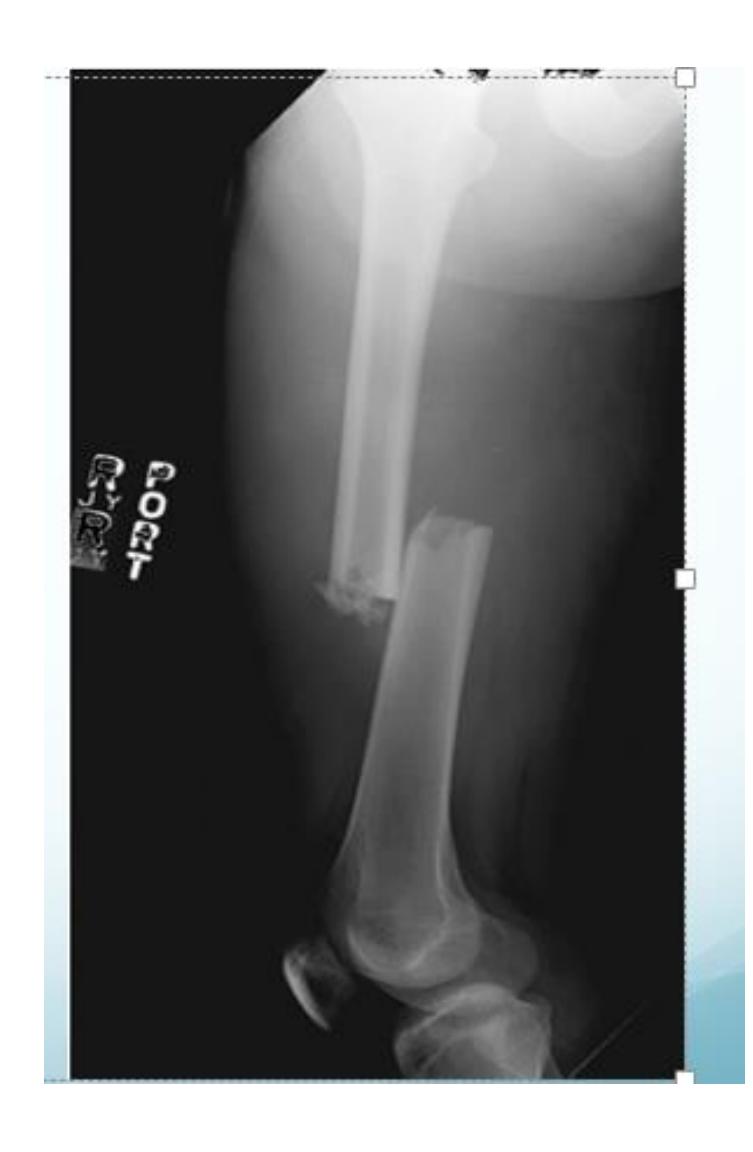

Which pattern of fractures is demonstrated in the attached X-ray?

- B. Segmental

Tibia and Fibula Fracture

Diagnosis: Segmental and comminuted fracture of tibia and fibula